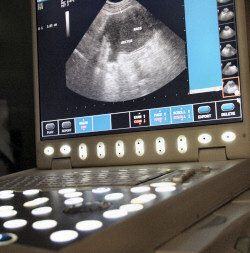

Ultrasound

Riverside Veterinary Hospital takes diagnosing your pet one step further by offering ultrasound services to pet owners in Sparta, Cookeville, Smithville, Livingston, Gainesboro, Crossville, McMinnville, and everywhere in between. Ultrasound is an extremely useful, non-invasive diagnostic instrument that produces clear, easy to read images that are more detailed than an x-ray.

The ultrasound allows our experienced veterinarians at Riverside Veterinary Hospital to visualize the structure and architecture of abdominal organs so they can find any abnormalities that cannot be seen or felt during an examination. It is used most often to diagnose bladder and kidney stones, discover abdominal masses, to aid in the assessment of organ function, to diagnose cardiac problems, and to evaluate pregnancies.

The ultrasound uses high frequency soundwaves to create a moving picture of your pet's internal organs. It sends sound waves into the area of interest where they may be transmitted through, reflected, or absorbed by the tissues they encounter. The ultrasound waves that are reflected will return as echoes to the device and are converted into an image giving a 2-dimensional picture of the tissues being examined.